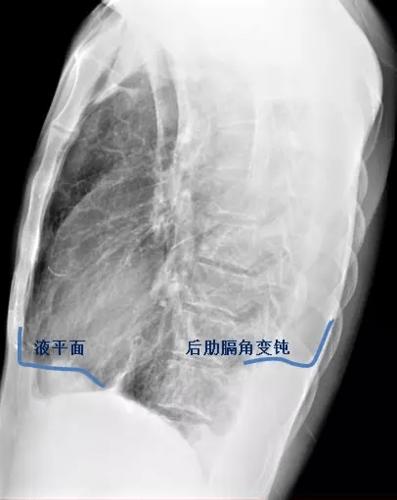

左下肺野可见液-气平面,约与第5前肋相平(蓝色虚线),肺门影不浓.

液平面